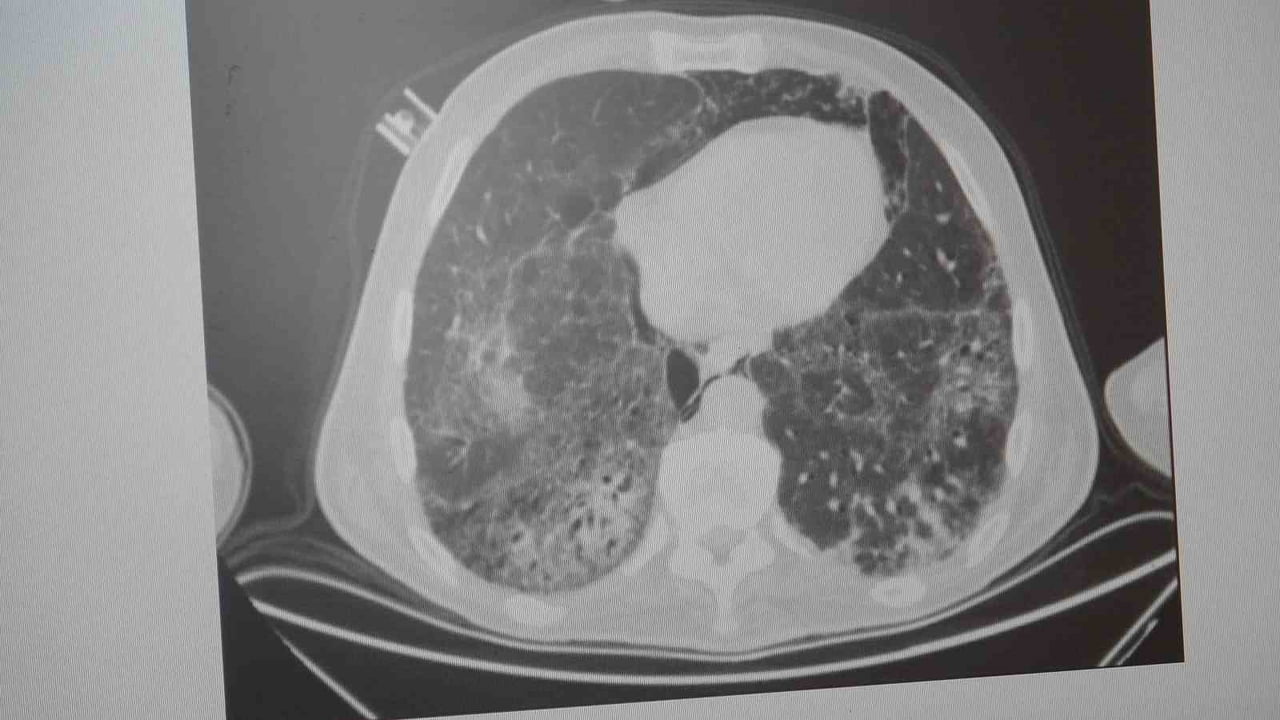

Karakurt, KOAH'ı zararlı maddelerin akciğeri tahrip etmesiyle ortaya çıkan bir hastalık olarak tanımladı. Buna ilişkin değerlendirmesinde, "KOAH önlenebilir bir rahatsızlıktır; sigaranın bırakılmasıyla birlikte tamamen ortadan kalkacaktır" ifadesini kullandı. Ayrıca hava kirliliği, iş yerlerinde kimyasal maddelere maruz kalma ve enfeksiyonların da KOAH nedenleri arasında yer aldığına vurgu yaptı.

Zatürre: Belirtiler, ayırıcı tanı ve riskler

Prof. Dr. Karakurt, KOAH'lı hastaların akciğer dokusu tahrip olduğunda enfeksiyonlara daha yatkın hale geldiğini ve enfeksiyonların daha güç geçebildiğini belirtti: "Akciğer dokusunun tahrip olduğu her durumda hastaların enfeksiyona karşı eğilimi artar ve enfeksiyona yakalandıklarında bunun geçmesi güç olur."

Zatürrenin belirtileri arasında öksürük ve balgam artışı, yüksek ateş (örneğin 38,5°C üzeri), artan nefes darlığı, titreme ve bilinç bozukluğu sayılabilir. Karakurt, bronşit ile zatürrenin ayırt edilmesinin önemli olduğunu; bronşitin daha çok bronşları, zatürrenin ise alveolleri (hava keseciklerini) etkilediğini vurguladı. Bronşitten ölüm nadirken, zatürrenin yaklaşık %10 civarında bir ölüm oranı ile seyrettiğini ve bu oranın yaşla birlikte arttığını kaydetti.